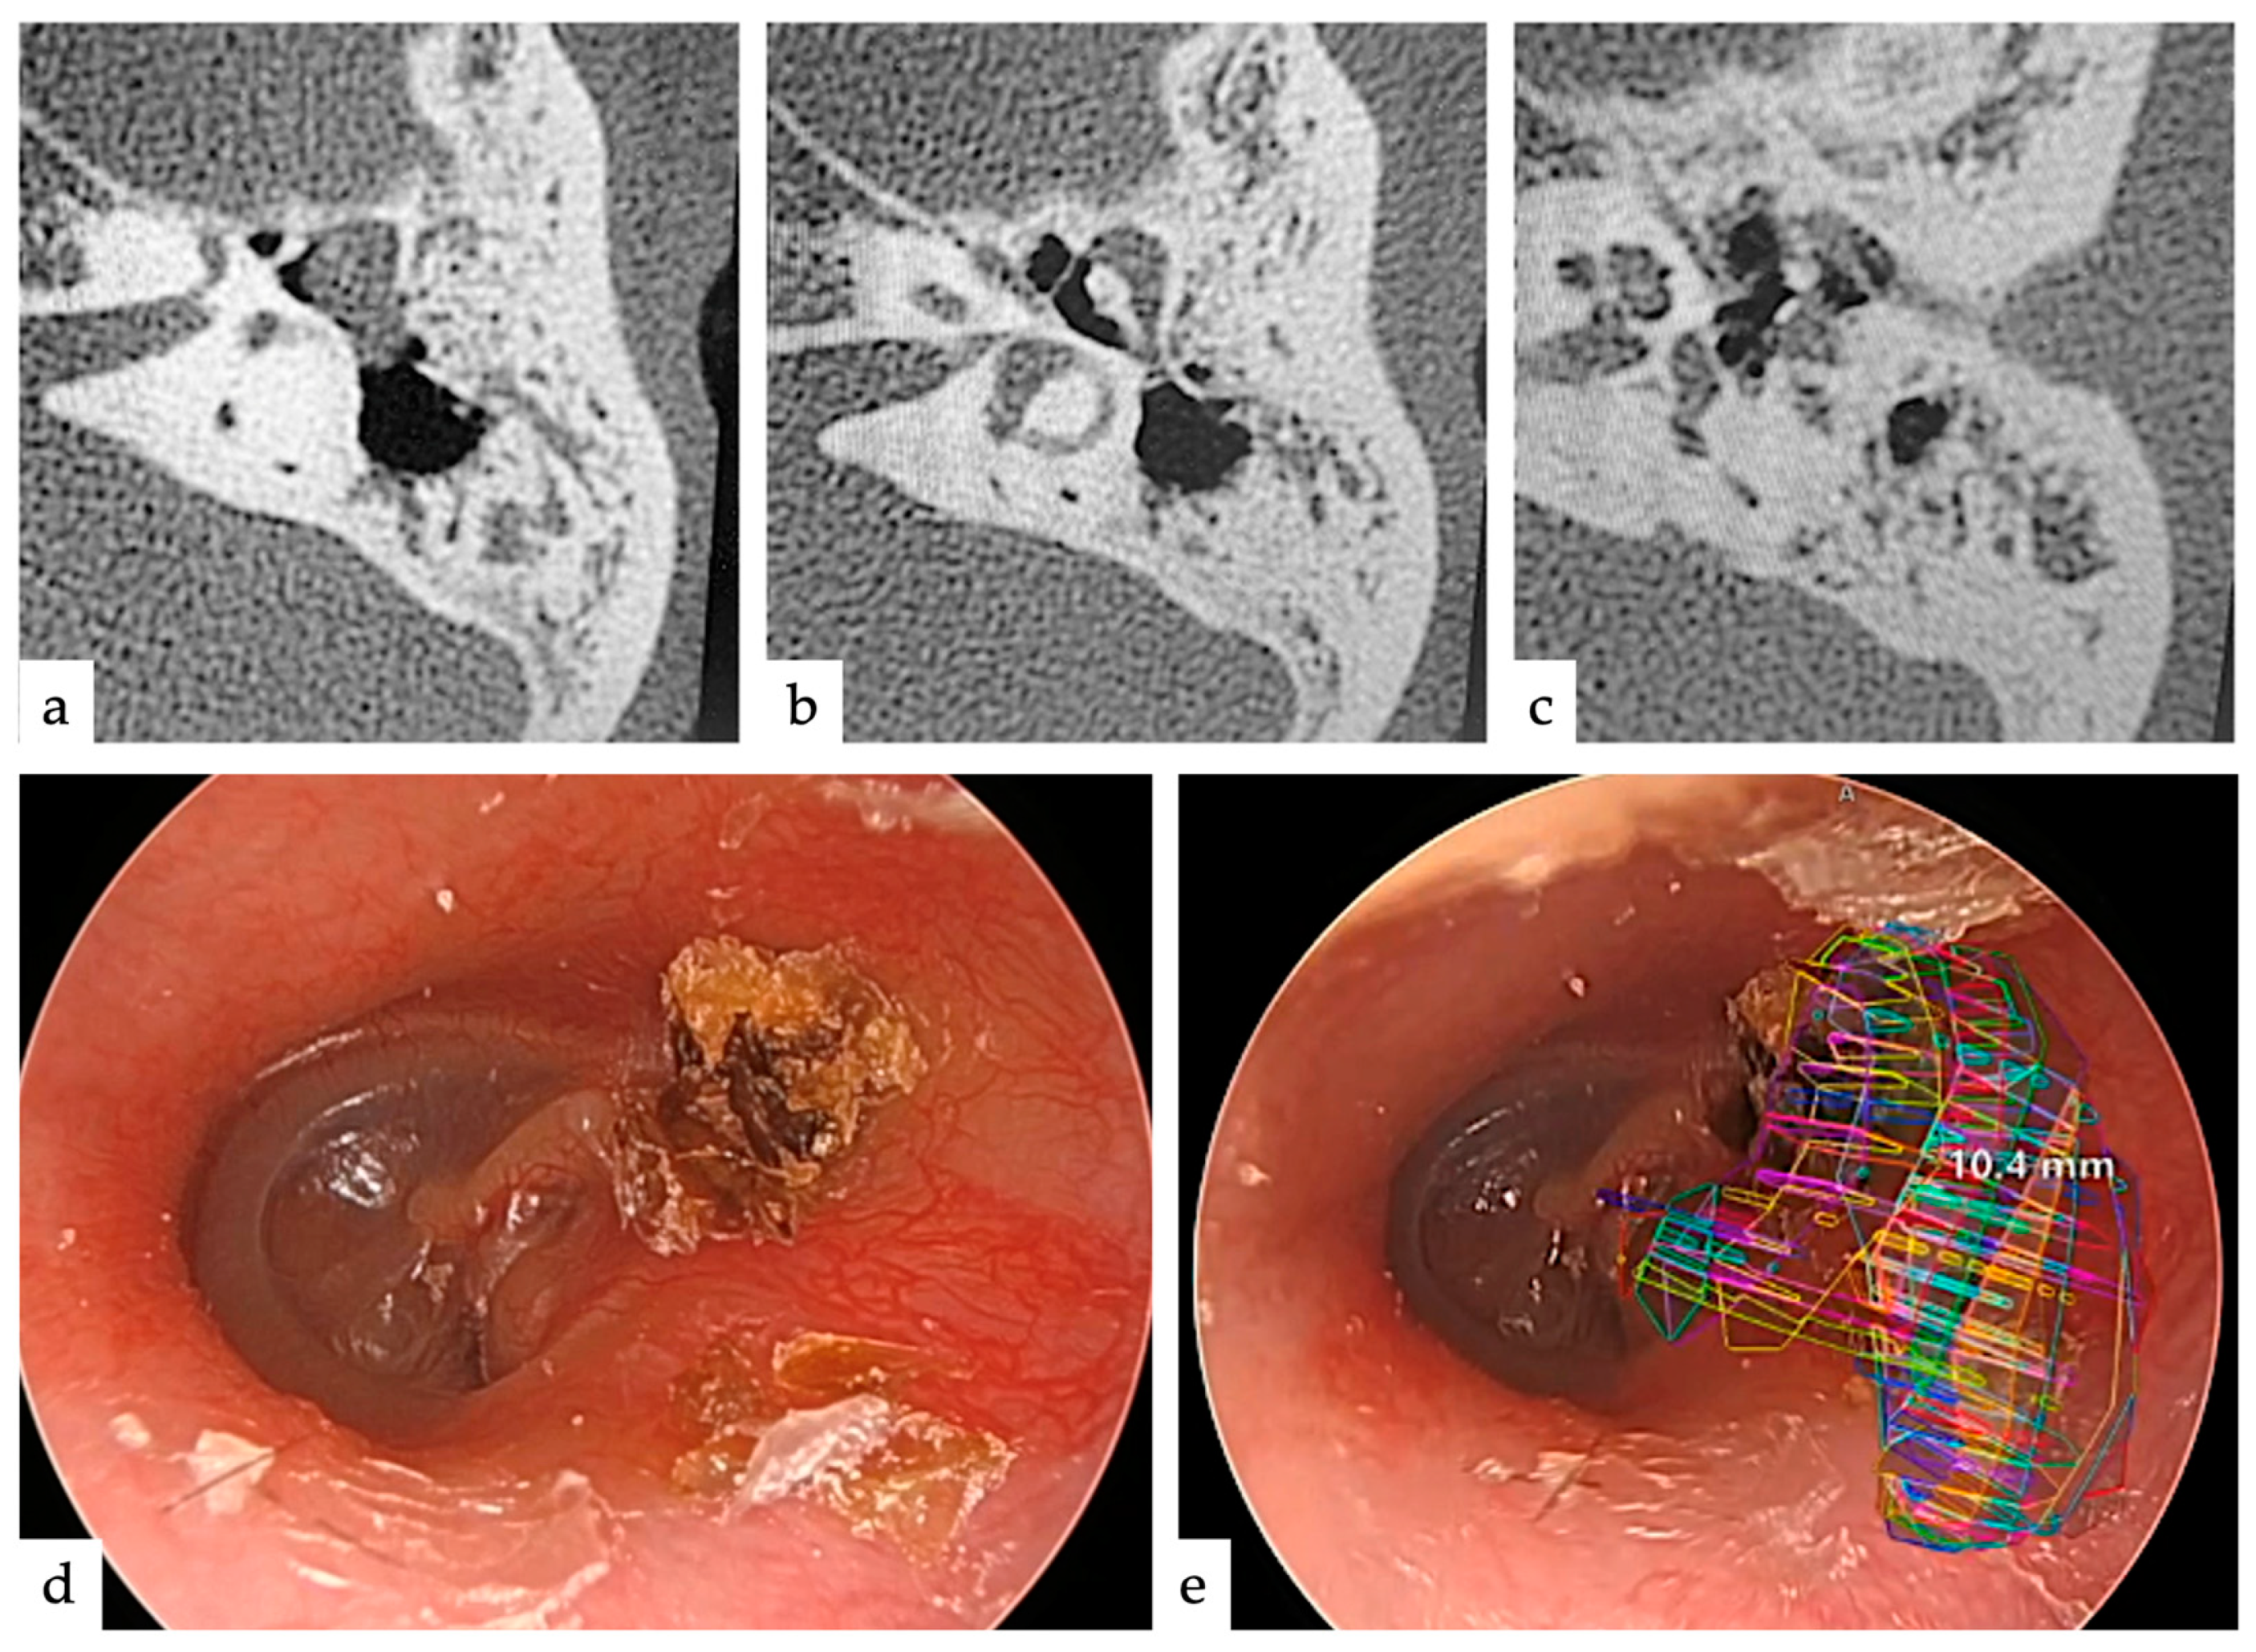

| Case | Age | Sex | Type | Range | TEES/MES |

|---|---|---|---|---|---|

| 1 | 44 | Male | pars flaccida | AM | TEES |

| 2 | 51 | Female | pars flaccida | TAM | MES |

| 3 | 41 | Male | pars flaccida | AM | TEES |

| 4 | 5 | Female | congenital | TAM | TEES |

| 5 | 41 | Male | pars flaccida | AM | TEES |